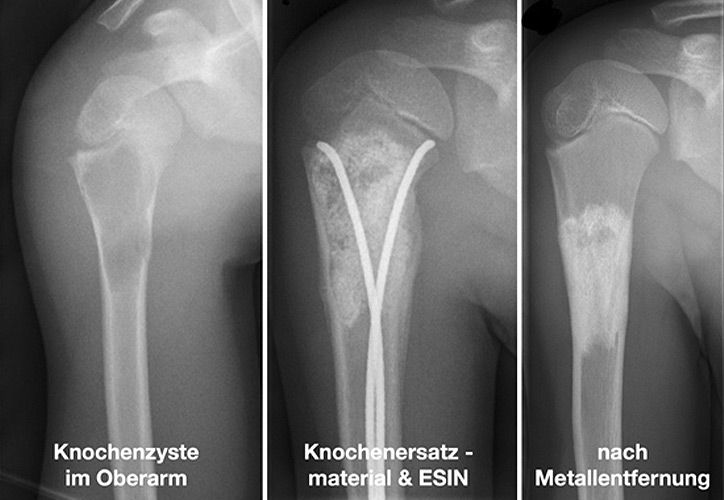

Knochenzysten sind die häufigsten gutartigen tumorähnlichen Knochenläsionen im Kindes- und Jugendalter und machen in großen Sammelstatistiken 13-19% dieser Läsionen aus. Es werden die juvenilen und aneurysmatischen Knochenzysten unterschieden. Der Altersgipfel für die meist zufällige Erstdiagnose liegt zwischen dem 9. und 13. Lebensjahr. Die Lokalisation der Knochenzyste verteilt sich nach Literaturangaben auf den Oberarm (ca 50%), den Oberschenkel (ca 30%), den Unterschenkel (ca 10%), aber sie können an allen Knochen vorkommen. Die genaue Pathogenese ist unklar, es werden jedoch lokale Wachstumsstörungen in der Entstehungsphase des Röhrenknochens diskutiert.

Um pathologische Frakturen zu verhindern, stehen mehrere Möglichkeiten zur Verfügung, z.B.: